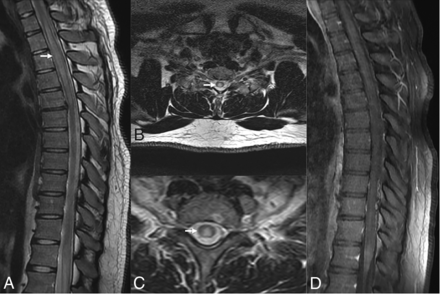

ATM is generally idiopathic or postinfectious immune-mediated demyelination, with EBV being a rare culprit.4,37,38 EBV myelitis is characterized by T2 hyperintensity in the spinal cord that extends over ≥2 segments covering equal or more than two-thirds of the cord, with the thoracic cord being the most affected (Figs 2 and 3). Enhancement patterns range from none to diffuse, with leptomeningeal and nerve root enhancement reported.37,39,40 EBV serologies can aid in diagnosing postinfectious EBV myelitis/ATM because MR imaging findings resemble those of other ATM etiologies. Spinal cord ischemia, MS, neuromyelitis optica, and autoimmune-related myelitis are imaging differential diagnoses for ATM. MS plaques usually affect less than one-half of the cord area and may have concomitant brain lesions. Spinal cord infarction shows bilateral anterior horn cell T2 hyperintensity symmetrically.38 Although rare in immunocompetent individuals, EBV ATM should be considered in cases of high CSF cell count atypical for idiopathic ATM.40

EBV-related transverse myelitis, EBV IgM–positive. T2-weighted sagittal image of the thoracic spine (A) and axial images (B and C) reveal diffuse long-segmental hyperintense signal (arrows) in the spinal cord more in the central gray matter region along with mild cervical cord swelling. No abnormal enhancement on the sagittal T1-weighted postcontrast image (D) was seen.